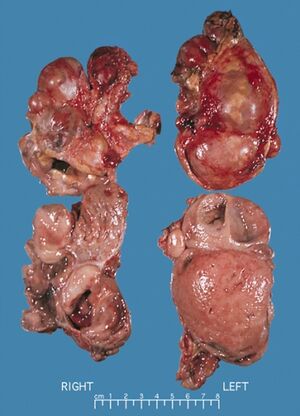

Bilateral pheochromocytomas associated with Multiple endocrine neoplasia type 2

يحدث ورم القواتم في 33-50٪ من حالات الورم الصماوي المتعدد من النوع 2.[3] في الورم الصماوي المتعدد من النوع 2 أ ، يحدث فرط نشاط جارات الدرقية الأولي في 10-50٪ من الحالات وعادة ما يتم تشخيصه بعد العقد الثالث من العمر. نادرًا ما يظهر في الطفولة أو يكون المظهر السريري الوحيد لهذه المتلازمة.[بحاجة لمصدر]يربط الورم الصماوي المتعدد من النوع 2 أ سرطان الغدة الدرقية اللبي بورم القواتم في حوالي 20-50٪ من الحالات وبفرط جارات الدرقية الأولي في 5-20٪ من الحالات.[بحاجة لمصدر] يربط الورم الصماوي المتعدد من النوع 2 ب سرطان الغدة الدرقية اللبي بورم القواتم في 50 ٪ من الحالات ، مع موطن مارفانويد والورم الليفي العصبي المخاطي والهضمي.

في سرطان الغدة الدرقية اللبي العائلي ، لا توجد مكونات أخرى للمرض.[بحاجة لمصدر] في مراجعة لـ 85 مريضًا ، كان لدى 70 مريضًا الورم الصماوي المتعدد من النوع 2 أ و 15 مصابًا بالورم الصماوي المتعدد من النوع 2 ب.[3] كان المظهر الأولي لـالورم الصماوي المتعدد من النوع 2 هو سرطان الغدة الدرقية اللبي في 60 ٪ من المرضى ، وسرطان الغدة الدرقية اللبي المتزامن مع ورم القواتم في 34 ٪ وورم القواتم وحده في 6 ٪. 72 ٪ لديهم ورم القواتم الثنائي